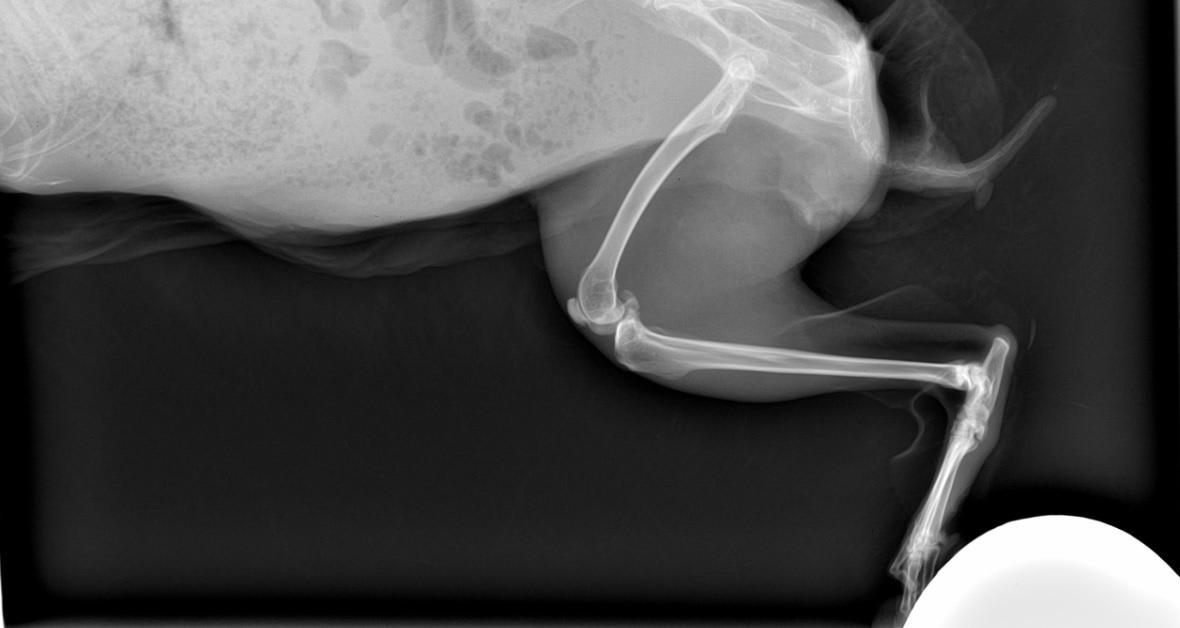

My rabbit's hind leg x-ray: Does it look normal to a veterinarian?

Pet's info: Small Animal | Rabbit | Female | spayed | 5 years and 2 months old | 4.1 lbs

Hello, I'd like someone to look at the xrays of my rabbit's hind leg and tell me if it looks normal.

Yes it seems normal to me but for full and thorough assessment another view of the leg (caudo cranial, or cranio caudal) should be ideally taken. Hope this answer was helpful, but please do not hesitate to contact us again on the forum or by requesting a consultation if you have any more questions or to discuss it any further.